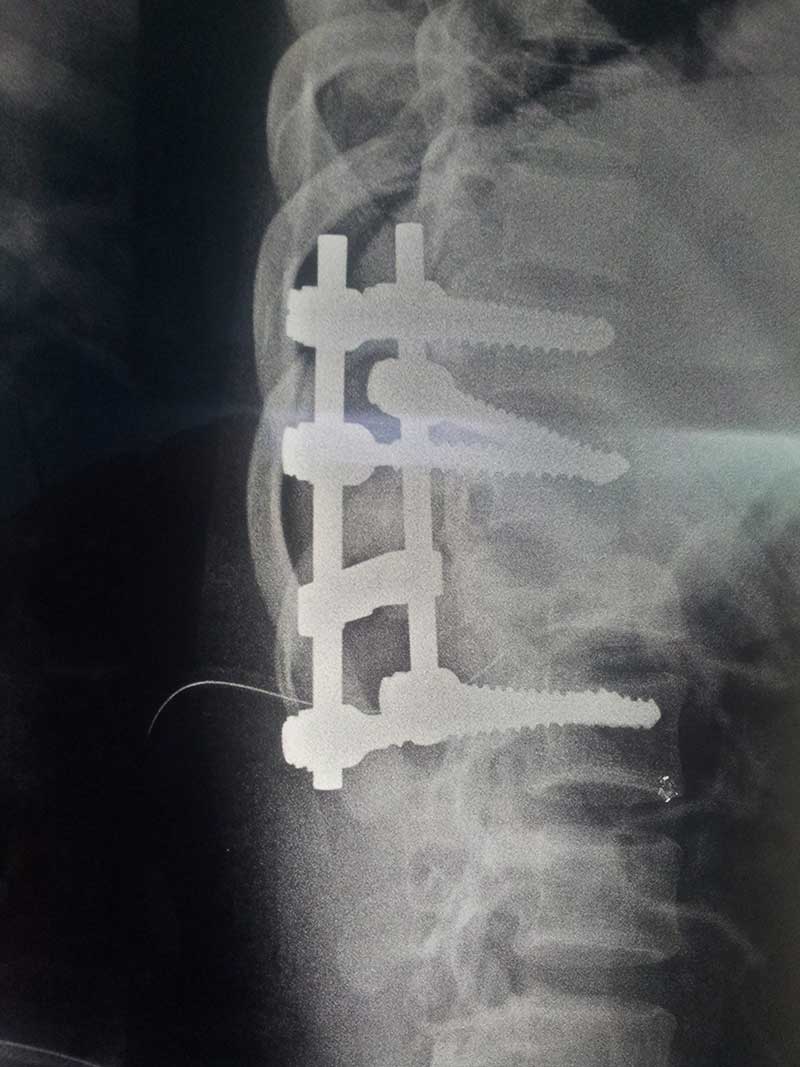

POST OP XRAY LAT

Spine Fixation Lumbar Spine

• Spine Fixation Lumbar Spine

post op x ray lat 1